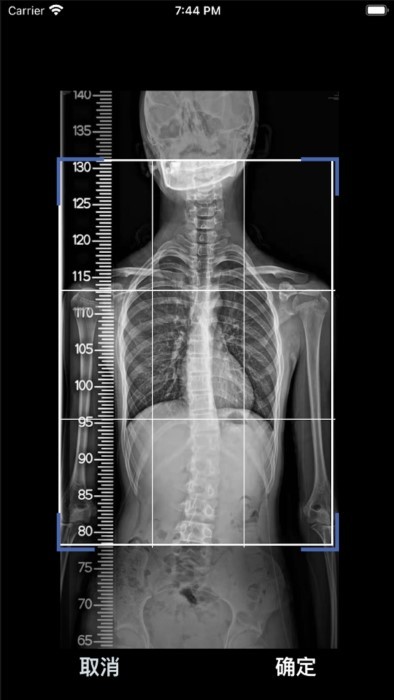

cobb角测量分析平台是一款功能强大的健康医疗类安卓软件,专为辅助医生进行脊柱角度测量而设计。该软件通过人工智能方式识别脊柱全长的x光片,模拟和显示测量后的结果和图像,帮助医生更准确地判断病人的脊柱侧弯情况。其简洁直观的操作界面和高效准确的测量功能,使得医生能够轻松上手,快速获取测量结果。

1. 上传影像图片:用户需要截取全脊柱x线正位片,并上传到软件中。为确保测量准确性,应避免图片中出现折痕、倾斜等问题。

2. 自动测量:软件会自动识别并测量脊柱侧弯的cobb角。用户也可以手动拖动端椎线进行角度校正,以提高测量的准确性。